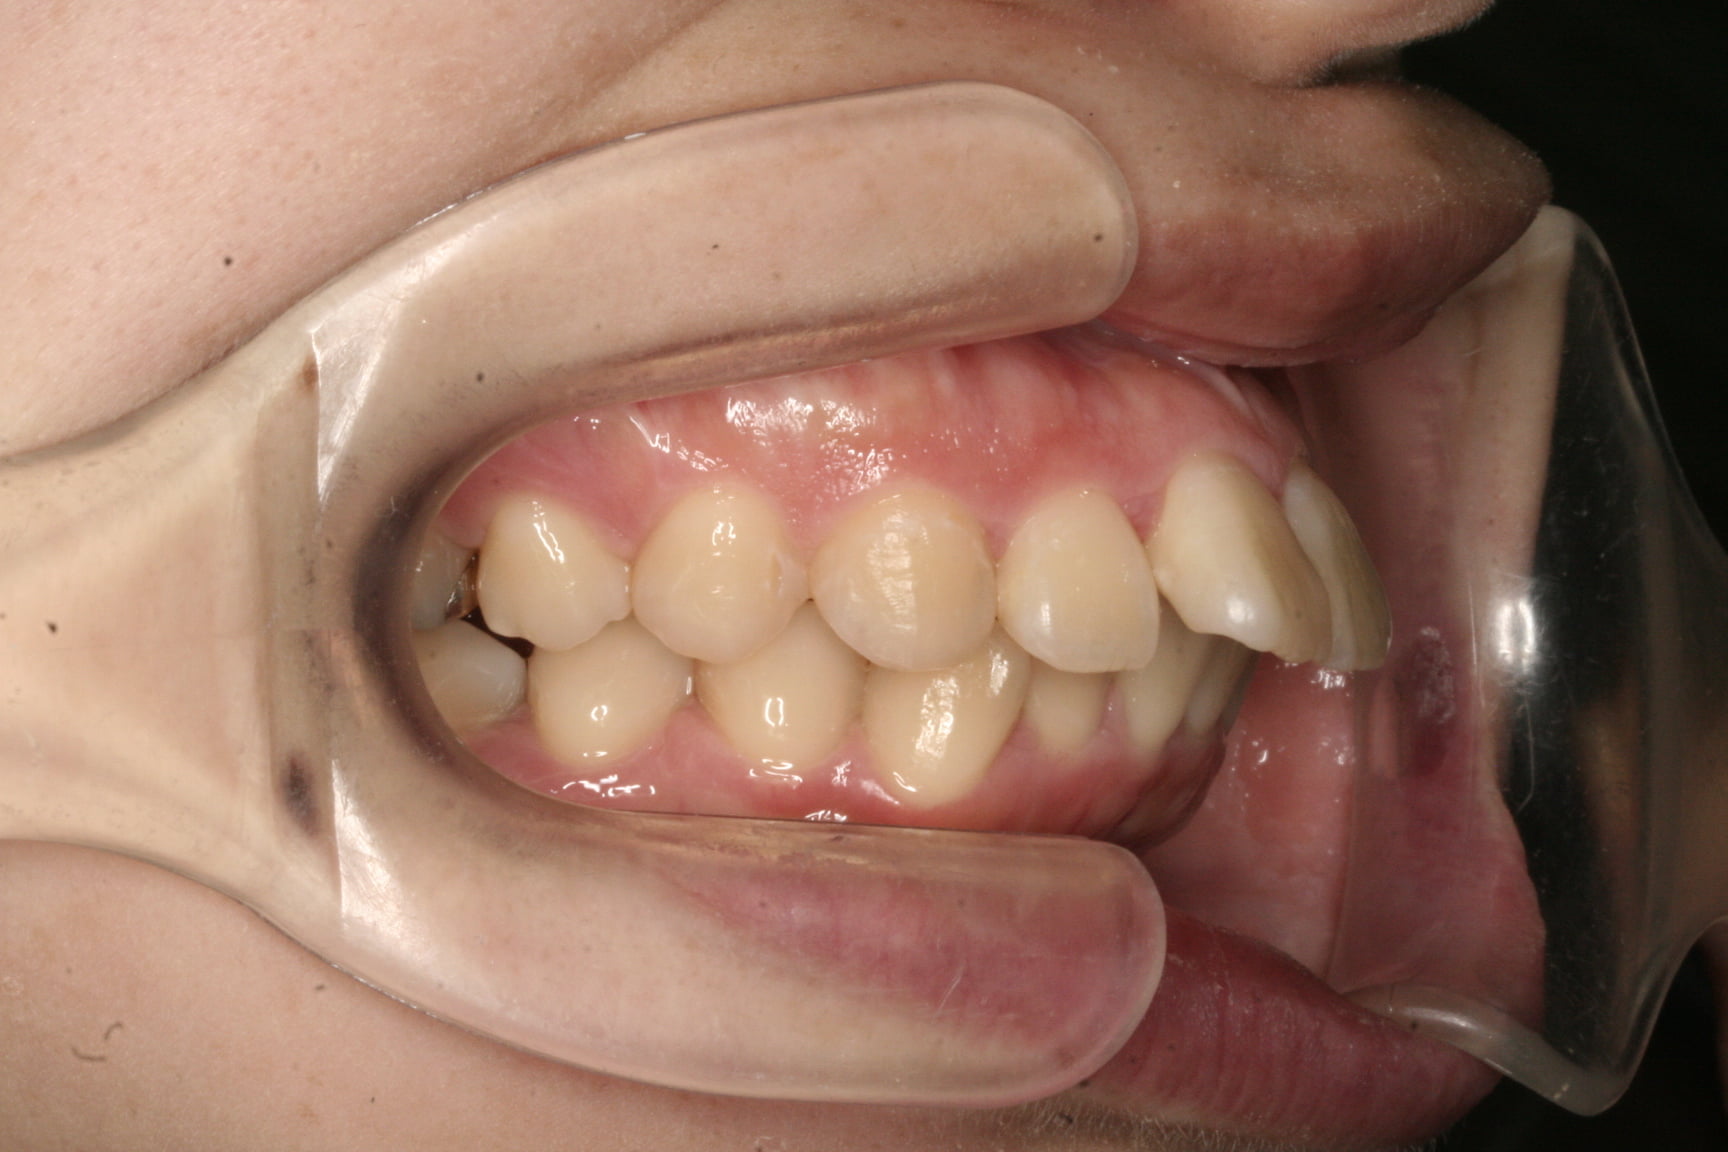

出っ歯を治したい

年齢層 30代

性別 女性

主訴 【主訴】出っ歯を治したい 【診断・症状】上下凸凹、口元が出てる

治療費用 検査・診断:38,500-/裏側矯正治療:1,397,000-(※全て税込)

治療期間 約2年9か月(36回)

抜歯 抜歯:有(上4,4)

矯正の装置 裏側矯正(舌側矯正)

副作用、リスク 歯肉退縮,歯根吸収,疼痛,咬合の違和感,装置の違和感,虫歯,歯肉炎

case21_出っ歯_before

Before

case21_出っ歯_after

After